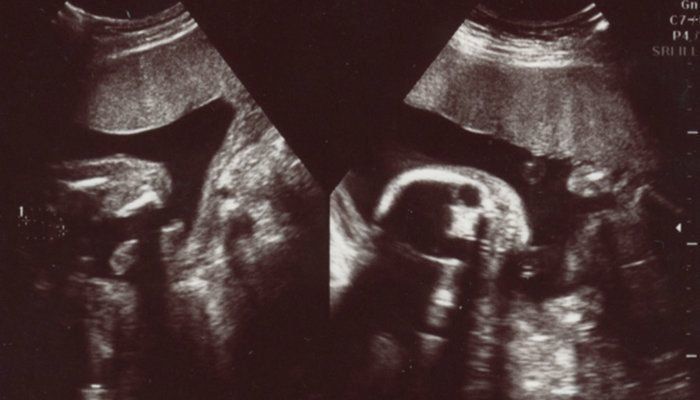

犬飼ねこさんの妊娠22週目のエコー写真

脳が半分に分かれているかのチェック。